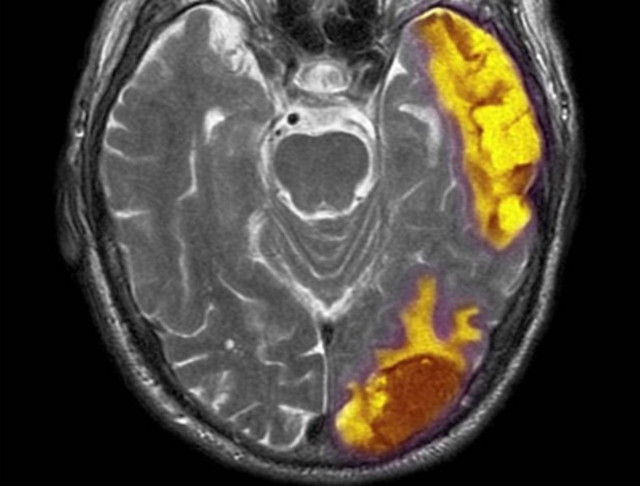

Το «σημείο του Θεού»

WHAT THE FACT · 24.04.2012 - 17:32

Το «σημείο του Θεού» βρίσκεται στον ανθρώπινο εγκέφαλο, υποστηρίζουν επιστήμονες από το πανεπιστήμιο του Μισούρι.